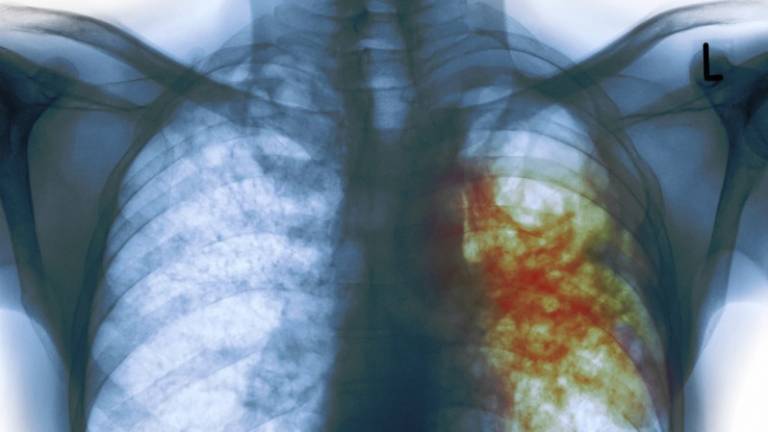

"Era muy frustrante, pero el último doctor particular que visité revisó mi radiografía y me dijo que probablemente era tuberculosis y ya en el Instituto Mexicano del Seguro Social (IMSS) me lo confirmaron", explica Gómez Coronado.

Castillo Rodal, quien forma parte del Departamento de Microbiología y Parasitología de la Facultad de Medicina de la UNAM, explica que 85 % de la tuberculosis es pulmonar y el resto se da en otros órganos o tejidos, y siempre ha sido un problema grave de salud.